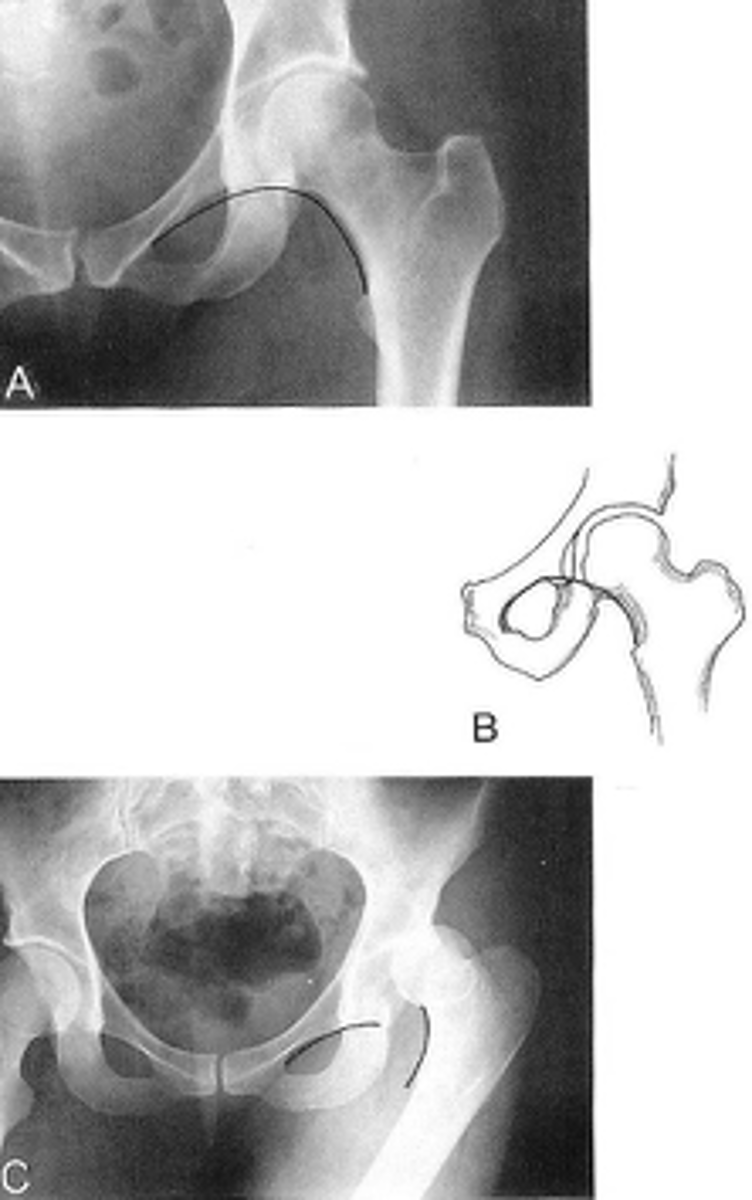

Shenton's line

ID measurement

<p>ID measurement</p>

- Smooth arc along femoral neck

- Obturator foramen

Shenton's line landmarks

<p>Shenton's line landmarks</p>

Continuous and smooth

Shenton's line normal measurements

<p>Shenton's line normal measurements</p>

62

- Hip dislocation

- Femoral neck fracture

- Slipped epiphysis

Clinical significance of Shenton's line

<p>Clinical significance of Shenton's line</p>